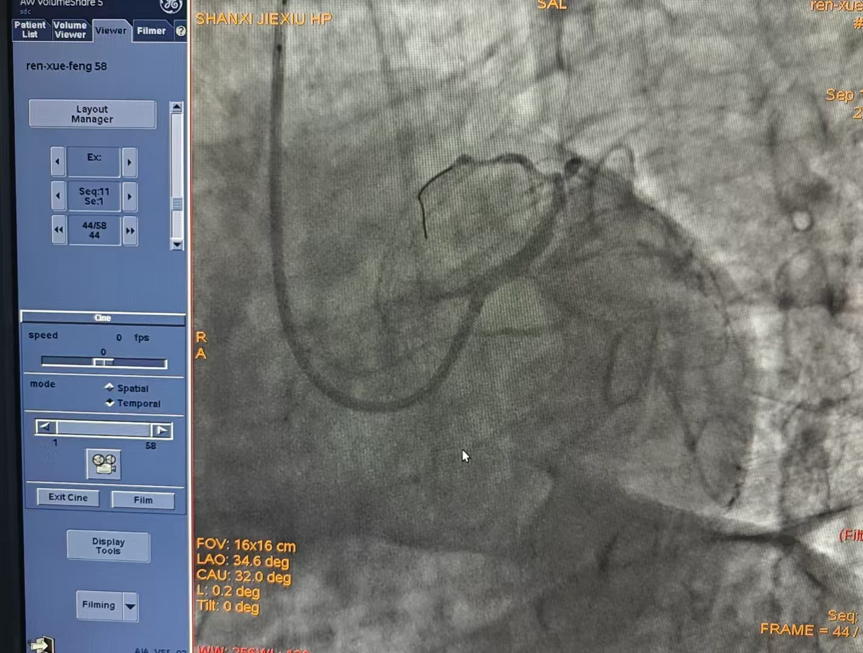

患者病情危急,手术过程复杂且凶险,在心内科手术医师及介入团队配合下仅仅使用20分钟即顺利完成整台手术,于左主干到前降支植入支架一枚,患者胸痛症状明显改善。